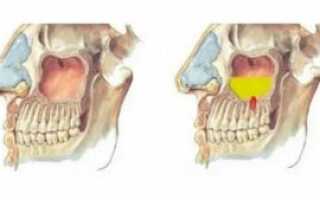

Посмотрите как это выглядит на схеме на примере гайморовых и лобных пазух.

Гайморовы пазухи (Г) имеют выводное соустье сверху, а лобные пазухи (Л) — снизу, это как бы перевернутые вверх дном бутылочки.

Эта схема, конечно же утрирована. В жизни все несколько сложнее…